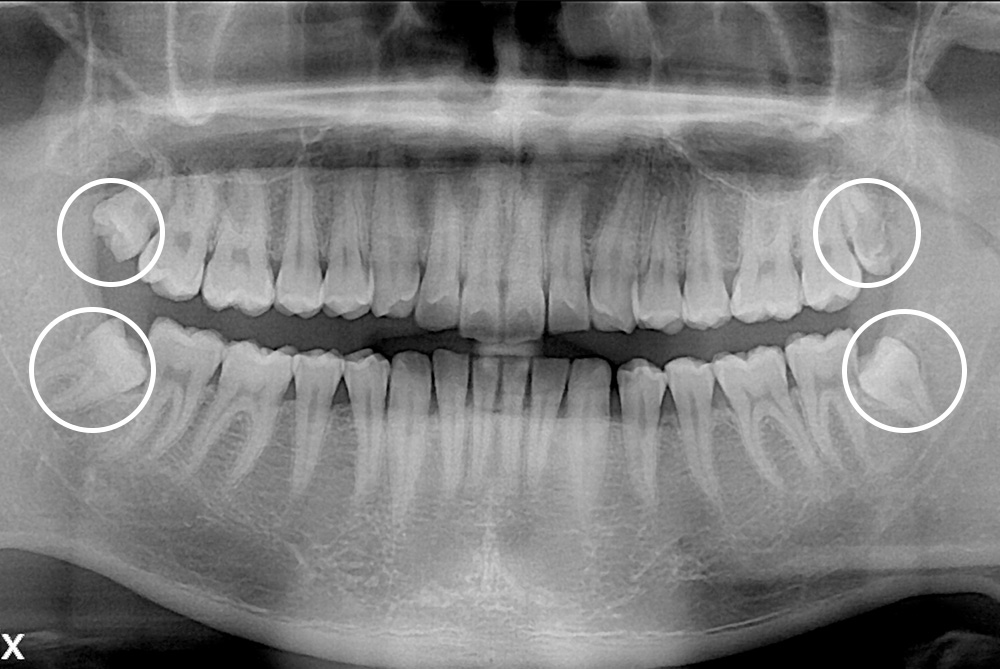

[사랑니] 매복 사랑니 발치

치료전 : 2019-05-02